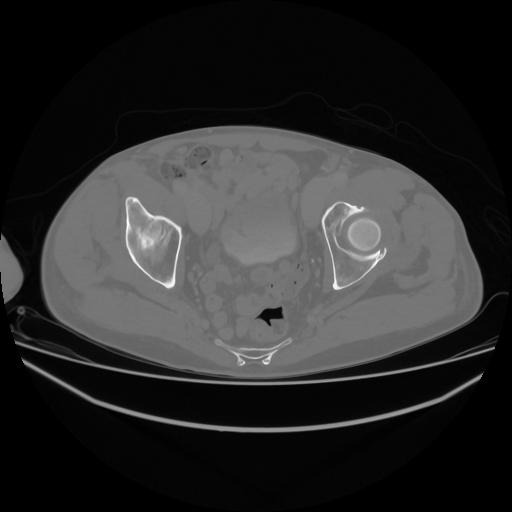

5 CUERPO,CE,Vol,1.0,CUERPO,,